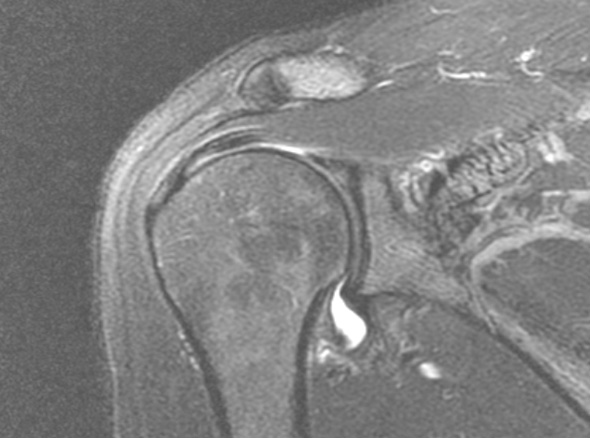

내시경을 통하여

유착된 관절낭을 유리화해 줍니다.

이러한 경우

내시경 시술을

고려합니다.

3-6개월 이상 보존적 치료를 하였으나 호전이 없는 경우

당뇨가 있는 경우

동반된 병변이 있는 경우 (석회, 충돌증후군, 회전근개 파열 등)

운동 범위의 감소가 매우 큰 경우